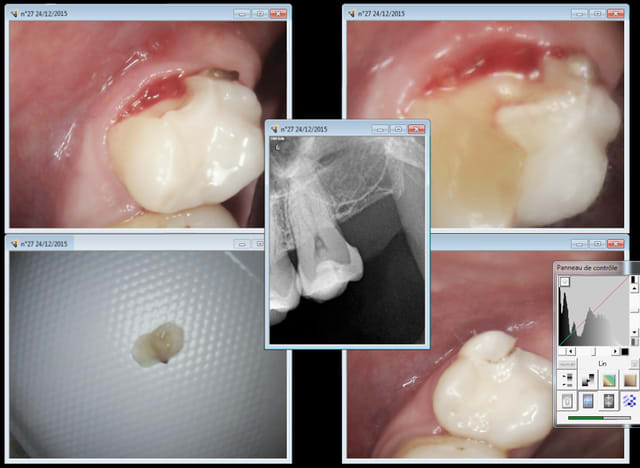

Patiente anglaise qui se pointe en urgence 27 fracturée. J'en lève le morceau et lui recommande de se faire dévitaliser sa dent et de faire une couronne ou de poser un onlay avec son dentiste de retour en Angleterre.

Comme la dent n'est pas douloureuse il n'y a pas urgence.

Je l'informe sur le montant d'une endo en France ( 81,94 euros) et là elle tombe littéralement des nues en Angleterre le tarif de son dentiste étant de 1000 livres.

J'ai eu l'impression de passer pour un cas soc en lui demandant 23 euros pour la consult ( c'est tout ? vous avez fait des photos radios une anesthésie pour virer le morceau cassé .....)

y avait peut être moyen de faire déjà élongation coronaire ou gingivectomie + éventuellement provisoire en vue couronne E max sur dent vivante, tu passais en NPC la patiente n'aurait pas forcément eut la même réaction...